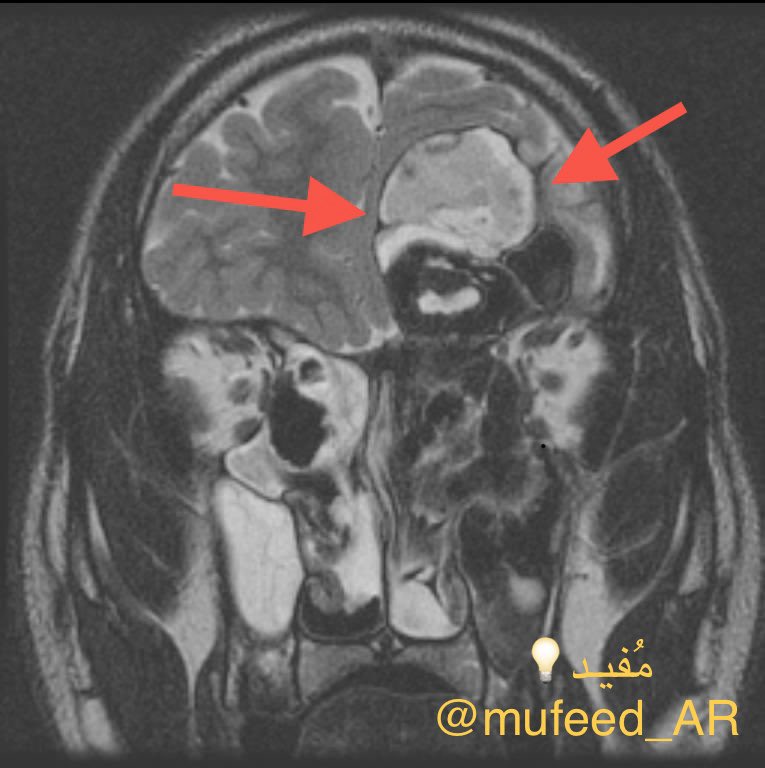

وقد تحتاج أشعة بالرنين المغناطيسي في حالة حدوث مضاعفات خطيرة مثل التهاب قاع الجمجمة، التهاب السحايا أو تكوين تجمع صديدي في المخ (تبين الصورة في الأسفل حالة التهاب فطري انتشر من الجيوب الأنفية إلى الدماغ).